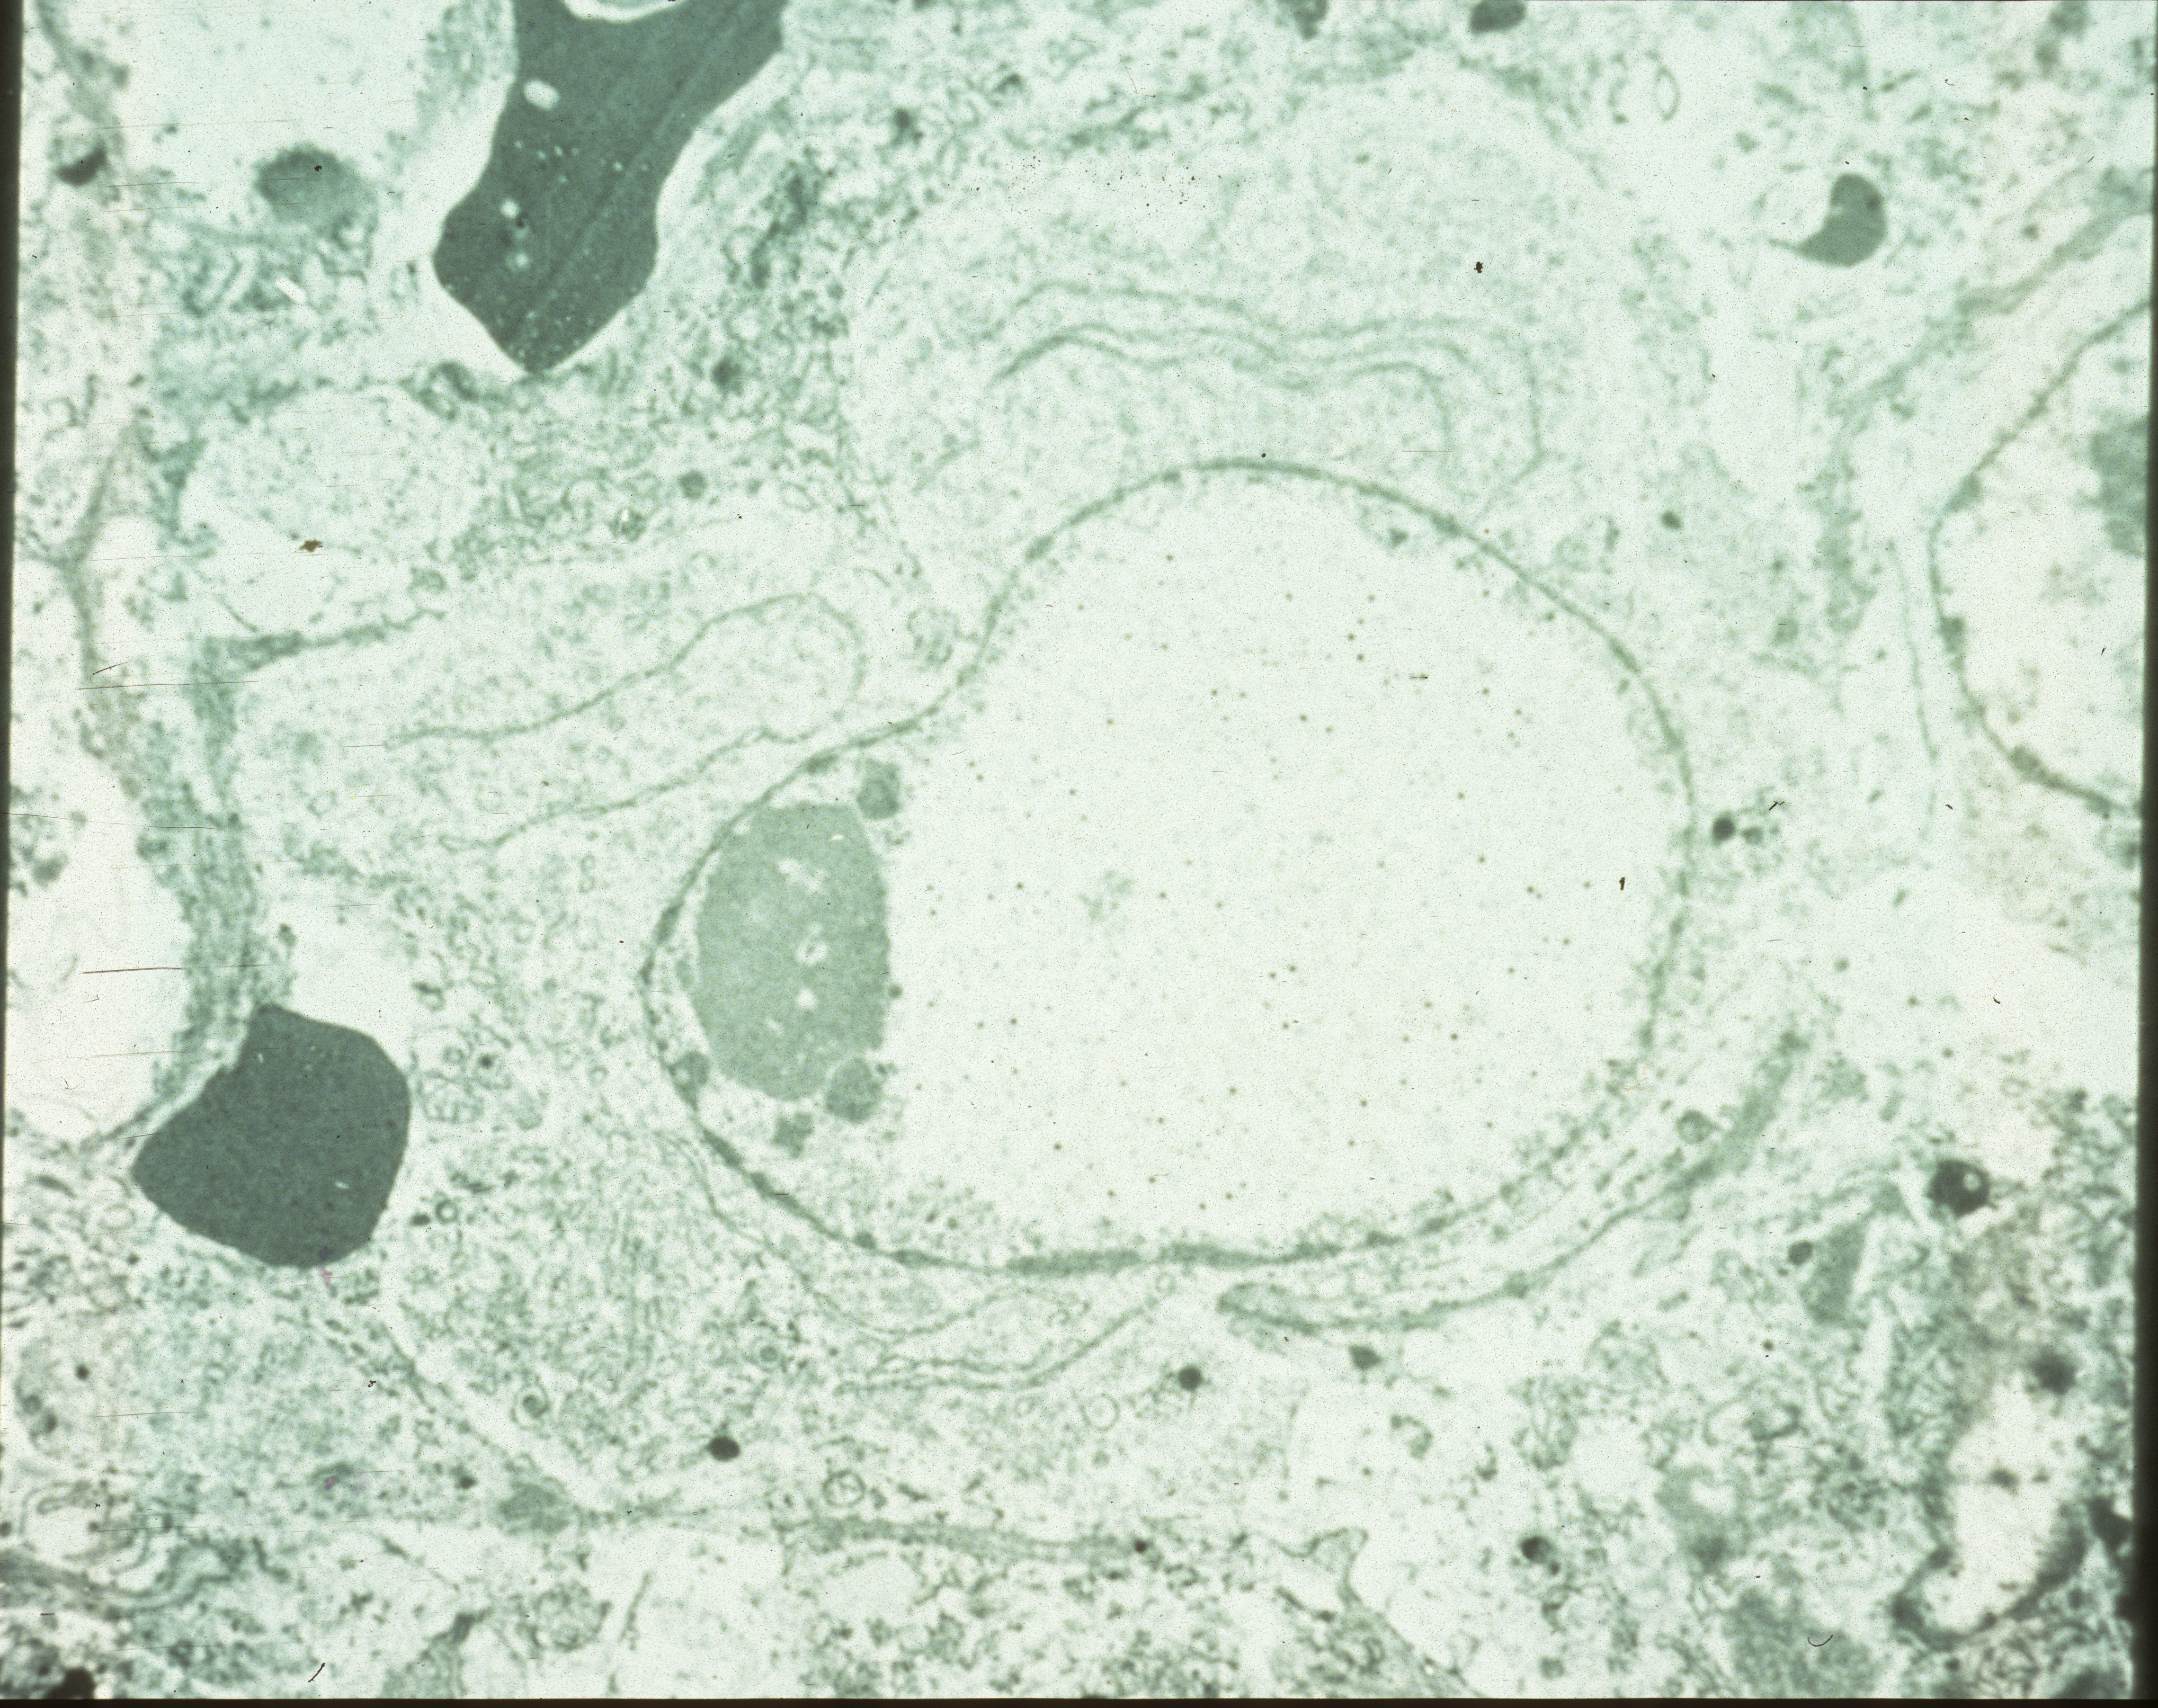

Marble spleen disease of ring-necked pheasants (slide study set no. 17) Item Info

Marble spleen disease of ring-necked pheasants (slide study set no. 17)

Slide study set #17, marble spleen disease of ring-necked pheasants, 2 sets (includes 40 color slides), undated